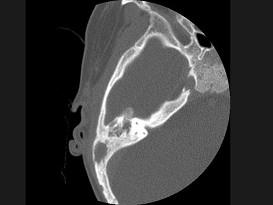

问题 女性,17岁,右耳乳突区隐痛,右耳后乳突区出现包块,逐渐增大,CT检查如图所示,请选择最可能的 ( )

选项 A、中耳癌 B、听神经瘤 C、化脓性中耳炎 D、嗜酸性肉芽肿 E、胆脂瘤

答案 D